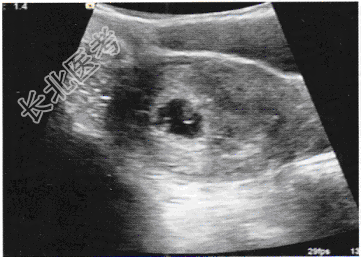

- 单项选择题女,23岁, 停经45天,阴道无异常分泌物, 子宫附件声像图见下图,图中所示为

A、正常早孕

B、宫腔积液

C、难免流产

D、子宫肌瘤

E、早孕并宫腔积液